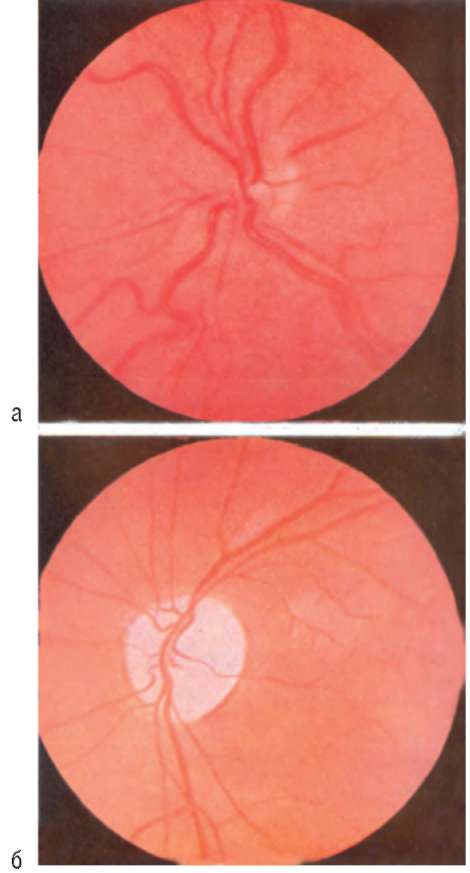

Рис. 12.2. Состояние диска зрительного нерва и его офтальмоскопической картины: а - в начальной стадии застоя - незначительный отек диска, расширение вен сетчатки; б - в стадии кульминации застоя - резкий отек диска с кровоизлиянием по краям, выраженное расширение и извитость вен; в - в стадии вторичной атрофии - диск уменьшается в размере, бледнеет, границы долго остаются нечеткими, вторичная (после застоя) атрофия диска зрительного нерва

Рис. 19.4. Симптом Ферстера Кеннеди - первичная атрофия диска зрительного нерва на стороне опухоли (б) и застойный диск зрительного нерва на другой стороне (а)